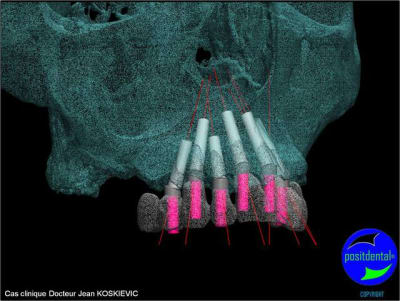

et la projet 10 implants maxillaire sup

10 en haut